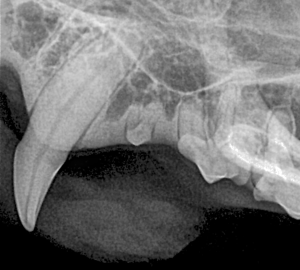

Canine Full Mouth Radiograph Example